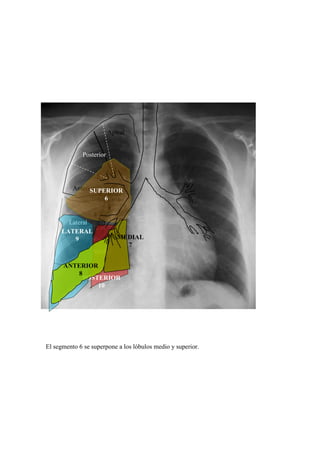

El segmento 6 se superpone a los lóbulos medio y superior.